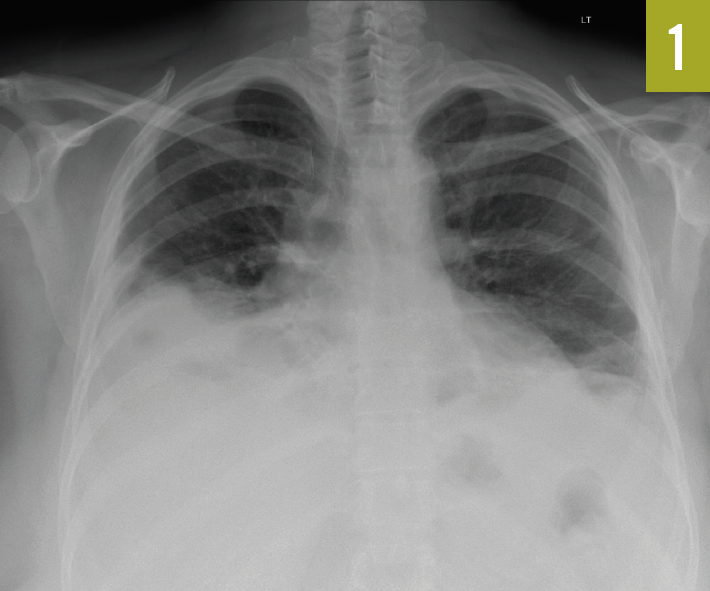

Here is a collection of 4 case reports about conditions affecting the lungs: fungal pneumonia, Legionnaire disease, rheumatoid lung nodules, and systemic lupus erythematosus.